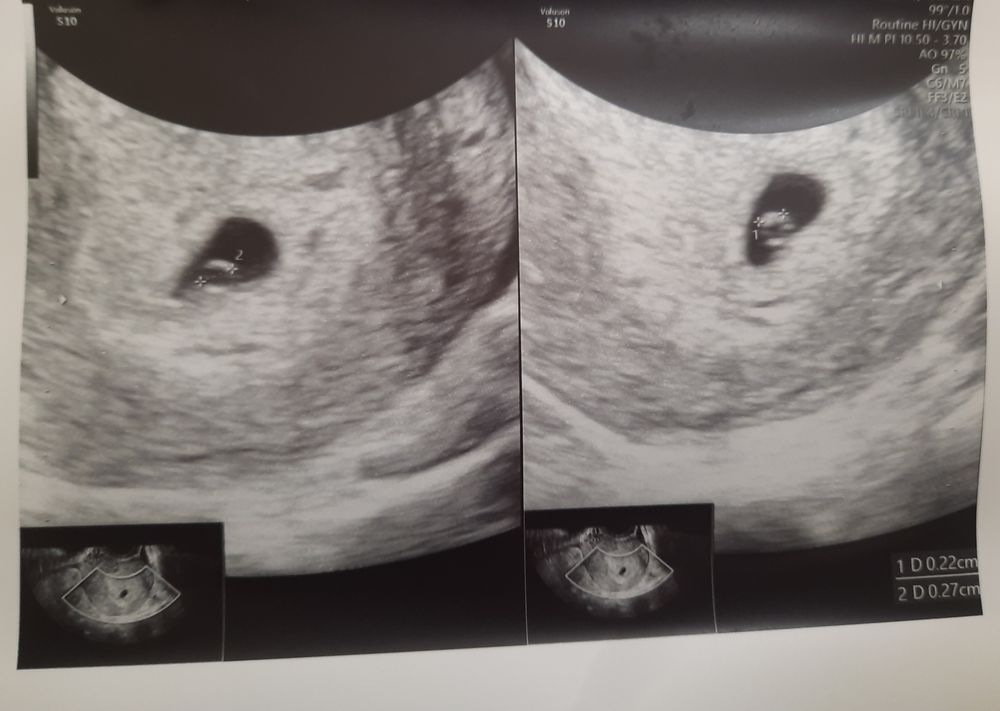

Первое узи, первая фотография 😃

Сегодня была на УЗИ, нашли мою бусинку там, где и надо, в матке 🤗🥹 ак срок 6-7нед, а по узи 3-4нед поставили, как и с дпо выходит сегодня 3нед и 3д. Контроль УЗИ назначали ещё через 10 дней, в середине апреля где та схожу сердечко послушать, тогда уже эм срок как раз 5-6 нед будет и сердечко будет слышно🥹 держись за мамочку крепко-крепко моя бусинка, мы тебя уже очень любим и ждём ❤️🥹 желаю всем ощутить на себе эти ожидания и радость от хороших новостей только 💞💞💞